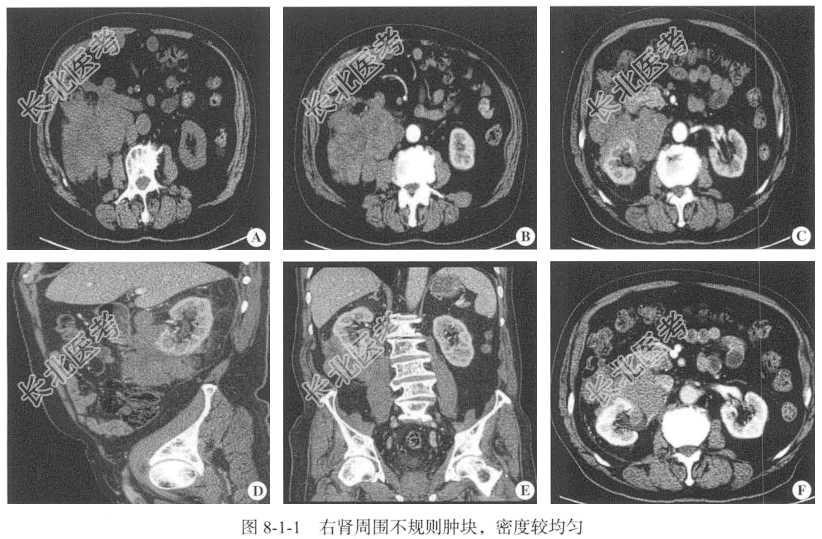

- [材料题] 【临床病史】男性,79岁。检查发现右肾占位性病变2周。

【泌尿系统CT检查】仰卧位,横断位扫描,行泌尿系统CT平扫,冠状位、矢状位及三维重建加增强扫描(GE64排CT机)。增强扫描采用高压注射器经肘静脉注射非离子型碘对比剂,总量85ml,流速3.0~3.5ml/s,于注射后30秒、70~80秒,3~5分钟行皮髓质期、实质期、排泄期增强扫描。

【影像图片】见图8-1-1。

【病理诊断】(右肾肿物穿刺)高侵袭性B细胞淋巴瘤,结合免疫组织化学可诊断为弥漫大B细胞肾淋巴瘤。